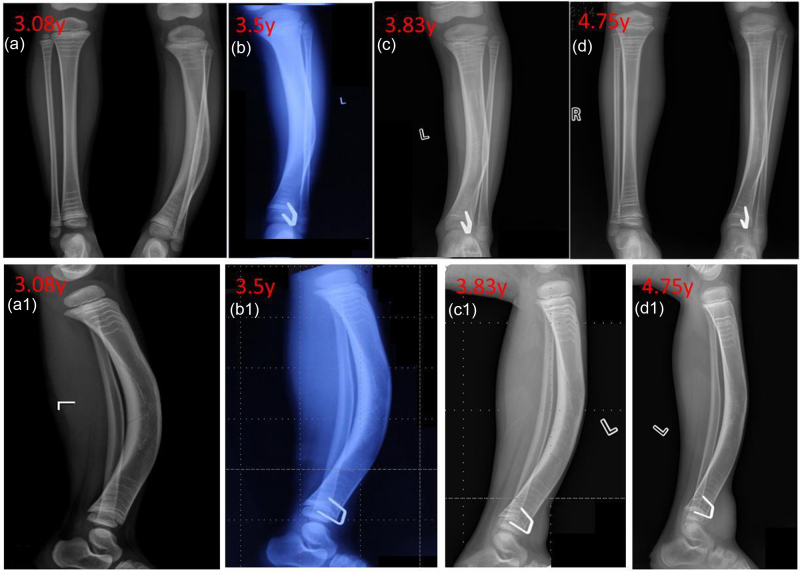

本研究的目的是探讨引导生长技术治疗儿童先天性胫骨前外侧弯曲(ALBT)的早期有效性。对2020年1月至2022年10月在两个中心接受“U”型钉引导生长技术治疗的18例ALBT患者进行回顾性分析。术前、取出植入物时或最后一次随访时采集双下肢、胫骨和腓骨的正侧位x线片。统计分析胫骨干骺端冠状角、矢状角、胫骨内侧近端解剖角(aMPTA)和胫骨外侧远端解剖角(alta)的变化,评价ALBT的矫正效果。所有患者平均随访23.36个月(14.53 ~ 37.2个月)。18例患者均表现出冠状面胫骨轴角的改善,平均矫正17.94°(范围:5.54°-33.52°)。14例患者矢状面胫骨轴角改善,平均矫正13.44°(范围:1.89°-32.6°)。治疗后aMPTA和alta水平均下降。随访期间,18例患者均未发生胫骨假关节。引导生长技术可以有效地改善ALBT,防止胫骨进一步的角度畸形,并可能延迟或预防胫骨假关节。此外,引导生长技术操作简单,微创,并发症少。

The aim of this study was to investigate the early effectiveness of guided growth techniques for managing congenital anterolateral bowing of the tibia (ALBT) in children. A retrospective analysis was performed involving 18 patients with ALBT treated with the 'U'-shaped staple-guided growth technique between January 2020 and October 2022 at two centres. Anteroposterior and lateral radiographs of both lower limbs and the tibia as well as the fibula were collected before surgery, at the time of implant removal, or at the last follow-up. Changes in the coronal tibial diaphyseal angulation, sagittal tibial diaphyseal angulation, anatomical medial proximal tibial angle (aMPTA) and anatomical lateral distal tibial angle (aLDTA) were statistically analysed to evaluate the correction effect of the ALBT. All patients were followed up for an average of 23.36 months (range: 14.53-37.2 months). All 18 patients demonstrated an improvement in the coronal plane tibial shaft angle, with an average correction of 17.94° (range: 5.54°-33.52°). Fourteen patients displayed an improvement in the sagittal plane tibial shaft angle, with an average correction of 13.44° (range: 1.89°-32.6°). Both the aMPTA and aLDTA levels decreased after treatment. No tibial pseudarthrosis occurred in any of the 18 patients during the follow-up. The guided growth technique is effective in improving the ALBT, preventing further angular deformities of the tibia, and may delay or prevent tibial pseudarthrosis. Moreover, the guided growth technique is simple to perform, minimally invasive and associated with few complications.